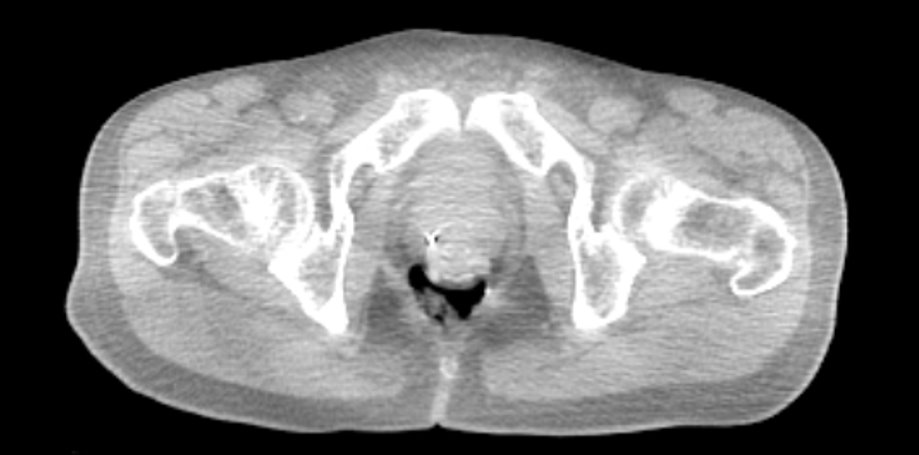

SpaceOAR Vue is a radiopaque hydrogel spacer that offers enhanced visiblitiy via CT scan, potentially helping physicians improve contouring accuracy and consistently position patients receiving prostate cancer radiation.1

Computed tomography image. Image provided courtesy of Gregory Merrick, MD.

The enhanced visibility on a CT scan is designed to help physicians improve contouring accuracy of the prostate and rectum, potentially leading to more accurate treatment plan creations when compared to SpaceOAR™ Hydrogel. This may reduce the overall treatment costs per patient, time required to fuse CT and MRI images, and the hospital staff’s time spent in obtaining MRI reimbursement authorisation.

For CT planning, physician-delineated prostate volume can be on average 15% smaller (under contouring) or 30% larger (over contouring) than the “true” prostate volume. With SpaceOAR Vue Hydrogel, you may be able to contour the prostate and rectum without the need for an additional MRI. This may also reduce any contouring inaccuracies, potentially leading to more accurate treatment plan creations. Accurate and consistent positioning of the patient from one fraction to the next is important to physicians, to ensure that treatment is delivered according to plan. CT radiopacity may provide an effective imaging option to MRI for patients with implanted metallic devices so you can care for a broader population of prostate cancer patients.